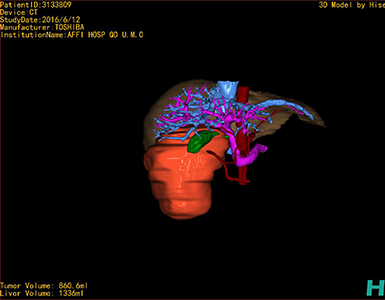

通过调节窗宽窗位调整CT序号,对肿瘤,肝实质,胆囊,下腔静脉,肿瘤,肝动脉、门静脉及肝静脉等进行三维重建;系统自动计算肿瘤体积和肝脏体积。

模拟手术操作,自动计算切除肿瘤体积。肝脏体积为1336ml,肿瘤体积为860.6ml,肿瘤体积为肝脏体积的64.4%,通过比对30-40岁正常肝脏体积为1323.35±298.47 ml,通过术前模拟手术,精准判断切除后剩余肝脏体积能耐受,避免肝衰竭发生。

术前三维重建:重建图片